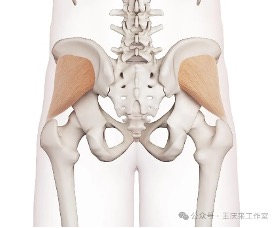

腰痛?屁股痛?你分清楚嗎?

腰痛?屁股痛?你分清楚嗎?腰痛?屁股痛?你分清楚嗎?通常提及腰痛,大家的第一反應都是腰椎間盤突出或者腰肌勞損。但其實在腰部的附近,還有一個常常被忽視的地方——骶髂關節,它的病變往往會引起腰痛及屁股痛。臨床上骶髂關節疼痛 (sacroil…查看詳情+